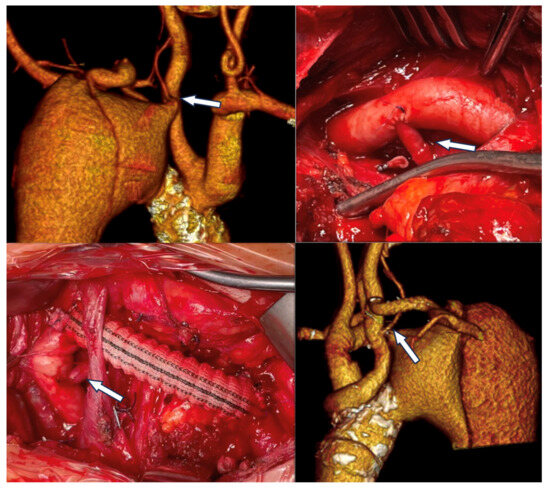

Several strategies for ILVA revascularization have been described in the included studies: the studies by Piffaretti et al., Yang et al., and Shergill et al. described the results achieved with ILVA open surgical revascularization during TEVAR (40 patients) [8,15]; the studies by Shen et al., Luo et al., and Wang et al. focused on total endovascular reconstruction through physician-modified fenestration (PMF) (39 patients) and in situ fenestration (ISF) (3 patients) [10,17,18]. Finally, Zhang and colleagues compared the outcomes of fenestration (24 patients), transposition (15 patients) and chimney technique (28 patients) for ILVA revascularization (Figure 3) [9].

Figure 3. Left vertebral to left carotid transposition and left carotid-subclavian bypass to achieve adequate proximal landing zone for endovascular treatment of a chronic post-dissection aneurysm of the thoracic aorta in a patient with a left vertebral artery arising directly from the aortic arch (arrow) in a patient treated at our institution.